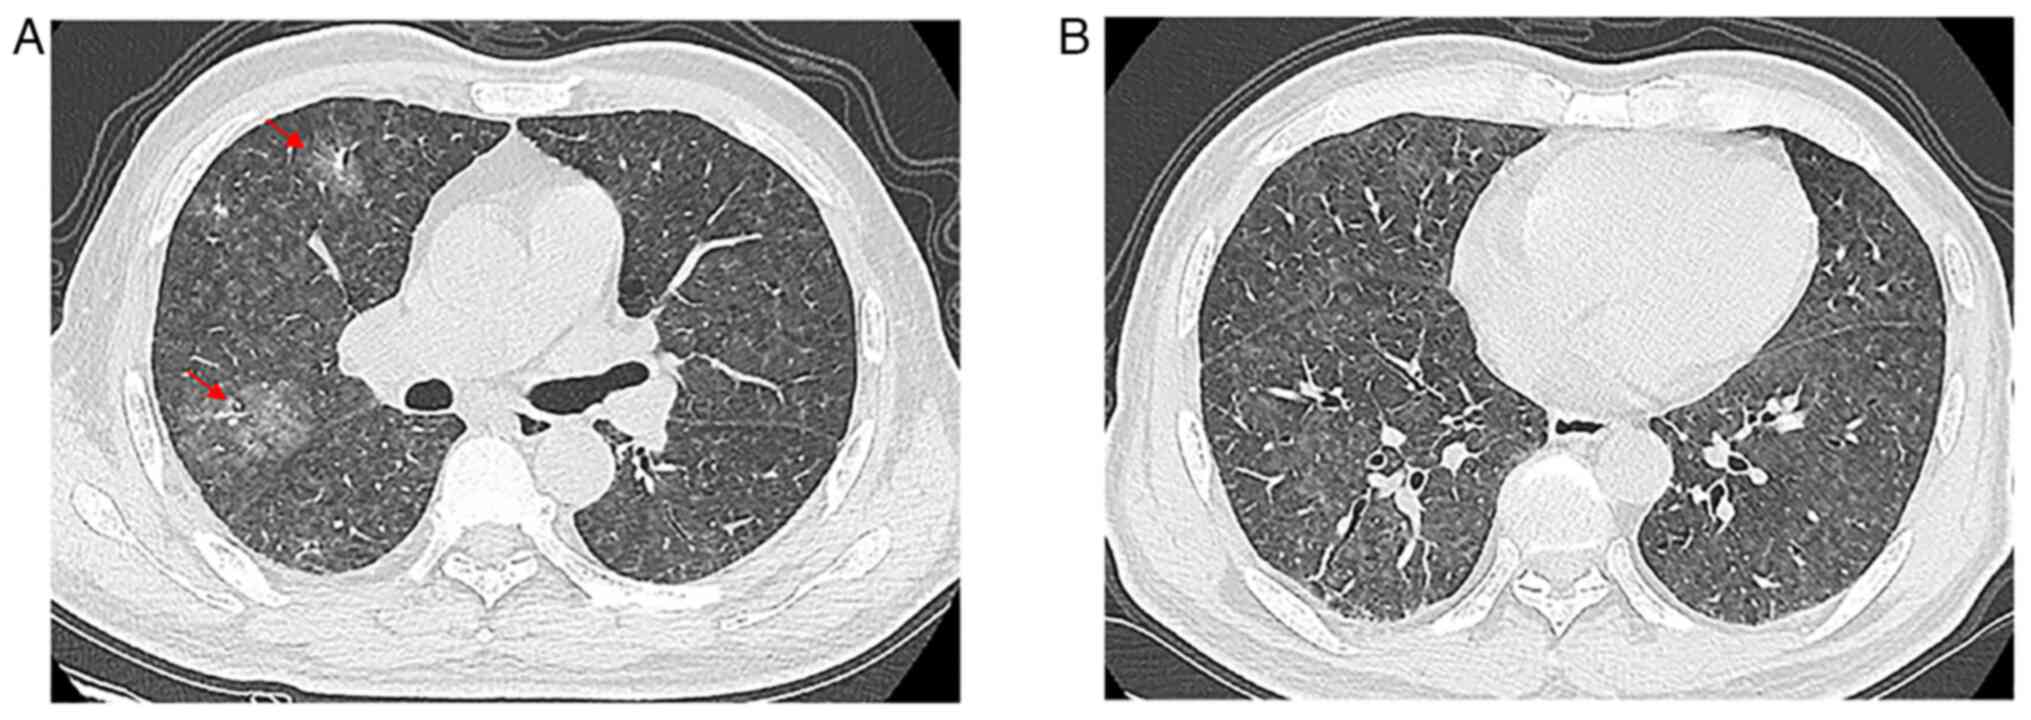

Case 4

A 60-year-old female patient presented at Nanjing Drum Tower Hospital in August 2015 with a 1-month history of progressive dyspnea and a 20-day history of intermittent high fever, with a maximum temperature of ~39°C. The patient had no history of lung disease and was a non-smoker. No cyanosis, clubbing, neurological abnormalities, nor cutaneous lesions were observed on physical examination. A high revolution chest CT (HRCT) examination was performed, and the images revealed pulmonary nodules with part-solid diffused GGOs in the lungs without pleural involvement (Fig. 4A and B). Additional examinations of whole-body CT examination yielded normal findings. The patient was diagnosed with interstitial pneumonia and the infection was treated with moxifloxacin hydrochloride (0.4 g/day) and sodium chloride injection solution for 7 days, and intermittent use of indomethacin (0.05 g) for antipyretic treatment, but the symptoms did not notably improve. Since there were no specific clinical or imaging findings and anti-inflammatory therapy failed, the patient underwent TBLB examination (of the superior lobe of the right lung). Light microscopy revealed a diffuse intravascular proliferation of atypical B cells and, combined with immunohistochemistry, IVLBCL was diagnosed. After a short period of glucocorticoids (40 mg methylprednisolone sodium succinate per day) treatment, the dyspnea initially improved, and the treatment appeared to be working. Unfortunately, the patient eventually discharged and gave up treatment due to a severe and uncontrollable lung infection.

Figure 4.

Case 4. (A and B) Axial computed tomography slices of the chest images revealed pulmonary nodules with part-solid diffused ground-glass opacities (arrows).

Compared with other pulmonary lymphoma, IVLBCL generally does not involve lymphadenopathy or a localizing solid mass, as the lymphomatous cells mainly involve the pulmonary arteries and capillary beds (14). Results of CT assessments are diverse and can be inconspicuous or show GGO and interstitial infiltration (11,12,14). In the cases of the present study, patchy areas of GGO existed on patient presentation and this accentuated the bilateral lung attenuation resulting from pulmonary vascular obstruction. In case 1, the chest HRCT revealed bilateral disease that was pneumonia-like, which progressed partly to consolidation. Due to local interlobular septal thickening along with the thickening of bronchovascular bundles, new GGO indicated lymphatic and hematological spread. The other 3 cases showed bilateral GGOs, micronodules and thickened interlobular septa in the lungs without pleural involvement, which suggested that the disease may spread along lymphatic structures. In case 2, the pulmonary shadows completely disappeared after a short-term chemotherapy schedule, which supported the diagnosis of IVLBCL. The etiology of GGO (heterogeneous and partially consolidated) in all four patients remains unclear. Malignant cells may invade the alveolar space, resulting in consolidation (increased density) on CT imaging. Increased diffuse density in bilateral lungs with GGOs and thickening of interstitial septum needs to be distinguished from non-neoplastic lesions, such as interstitial diseases and mechanical pneumonia, which may also present as progressive dyspnea with cough and other manifestations of obstructive ventilation. TBLB and bronchoalveolar lavage fluid can be used to aid diagnosis. Undoubtably, IVLBCL needs to be differentiated from venous thromboembolism and other intravascular malignancies of the lung, including lymphomatoid granulomatosis, angiocentric lymphoma and pulmonary involvement by acute and chronic lymphocytic leukemias (3). At this point of the patient examination, the clinical manifestations and CT characteristics may be non-specific, and immunohistochemistry will provide great help for the correct diagnosis.